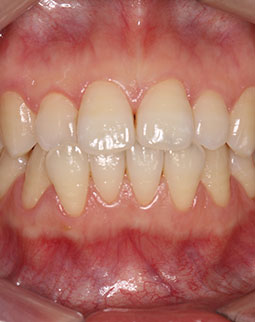

过去的困扰

说起我的矫牙之路真的是一波三折,我真的等了6年!在读护理专业的时候,因为牙齿不好看,显得嘴凸,我就想想通过矫正把牙齿排齐,无奈当时并没有什么钱。后来升职加薪后就更关注自己的外貌,然而动辄上万元的矫牙费用,对于毕业没几年尚无积蓄的我来说是一件奢侈的事,但是矫牙的念头在我心里植下了根。

2014年,即将步入婚姻的殿堂,希望有口漂亮的牙拍出美美的婚纱照,只是隐形牙套尚未普及,实在接受不了丑丑的钢牙!婚后经济实力都可以,想矫牙的时候发现自己怀了宝宝,怕孕期影响到宝宝健康,又搁置了......

孩子也快两岁了,终于可以安心矫牙了,当麦芽正畸医生给我介绍隐形矫正,并提到麦芽双膜隐形牙套可以提升矫牙速度30%时,其实内心有点激动又有点小遗憾,因为如果早知道有麦芽双膜隐形矫正这回事,我就能在结婚前把牙齿排齐了,拍出美美的婚纱照了!